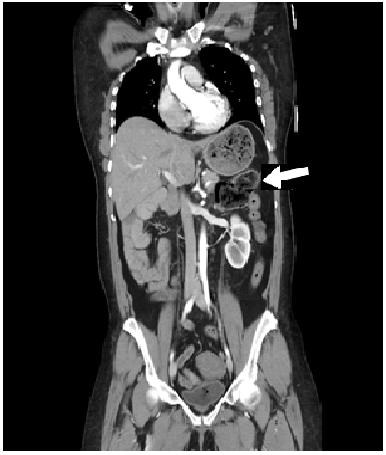

A 50-year-old female without any significant past medical or surgical history presented to the emergency room after being involved in a pedestrian versus automobile accident. The physical exam was unremarkable. CT scans of her abdomen revealed that the cecum and ascending colon (Figure 1, arrow) were located predominately on the left side. Also, the superior mesenteric vein and the superior mesenteric artery were inverted in respect to their normal anatomic relationship with the superior mesenteric vein being located to the left of the superior mesenteric artery instead of to the right as in their normal anatomic configuration (Figure 2, arrow) which is a diagnostic of congenital malrotation. She was discharged after 24-hour observation and remained asymptomatic.

Figure 1: Abdominal CAT scan (coronal view) demonstrating the cecum and ileum malpositioned in the left upper quadrant in the usual location of the stomach.